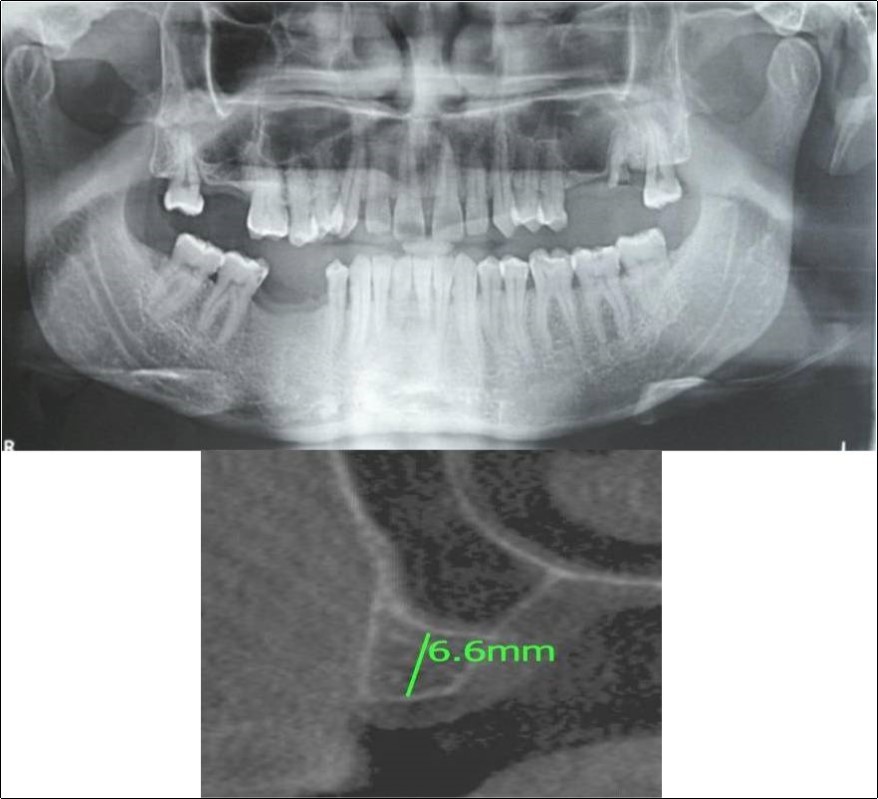

Case Report 3:

A 75 years old male patient reported to the Department of Oral and Maxillofacial Surgery, D.A.P.M.R.V Dental College and Hospital seeking options for replacement of his missing tooth in right upper back tooth region with a fixed prosthesis. The tooth was extracted around 10 years ago because of pain and infection associated with the tooth. No prosthetic rehabilitation was carried-out in the past. 16 was found to be missing and the patient reported that healing was uneventful post-extraction of the tooth. The patient was a controlled diabetic and hypertensive and was on medications for the same. Patient did not give history of any existing sinus pathologies. All possible rehabilitative options were explained to the patient and a treatment plan of replacement of missing 16 with implant supported prosthesis using one dental implant was finalized

Clinical and Radiological Assessment:

1.Partially edentulous maxillary arch with missing 16;

2.Increased pneumatisation of right maxillary sinus;

3.Height of available bone- 5.3mm;

4.Transverse thickness of available bone (CBCT evaluation)- 10.2mm;

5.Inter-ridge space adequate to place implant (10mm).

Treatment:

Patient underwent the procedure of indirect sinus elevation using sinus osteotomes in relation to 16 region. Calcium phosphosilicate putty was dispensed as the graft material through the crestal osteotomy site to maintain the elevated sinus membrane followed by placement of a dental implant measuring 5 x 10mm under local anaesthesia and strict aseptic protocols. The implant was allowed to osseo-integrate for a period of six months during which the patient was followed-up periodically and was assessed for peri-implantitis, crestal bone loss and mobility. At the end of 6 months, a repeat CBCT scan was advised to evaluate the increase in bone height. (Figure 11a,b, pre-treatment; Figure 12a,b, post-treatment)

Figure 11.(a,b) Pre-treatment OPG and cross section of CBCT showing residual alveolar bone height for Case No.3

Figure 12.(a,b) Post-treatment OPG and cross section of CBCT showing residual alveolar bone height for Case No.3;